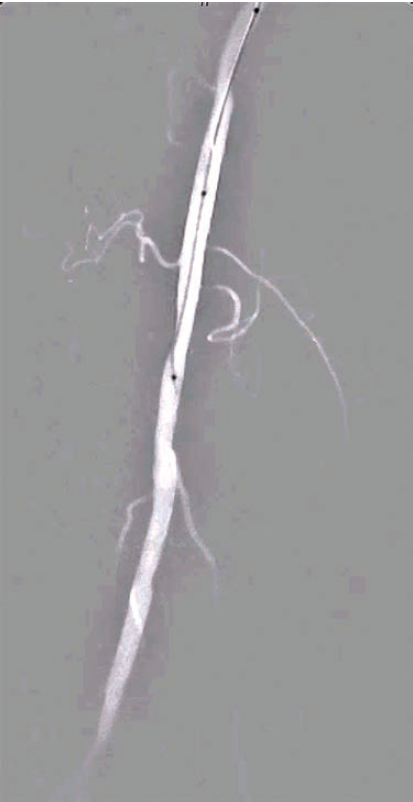

The development of roadmap imaging has further refined the guidance of endovascular interventions. By generating a real-time, detailed overlay of vascular anatomy aligned to live fluoroscopy, roadmap imaging enables more precise and accurate navigation during these procedures, thereby reducing the risk of complications as well as improving patient outcomes.

Roadmap imaging represents a sophisticated blend of pre-acquired images (often from computed tomography [CT] angiography or DSA) with real-time fluoroscopy, providing a continuous overlay that allows for precise guidance throughout the procedure. The technology works by creating a “virtual road” overlaid onto live fluoroscopic images, facilitating catheter and device navigation.

2. Reduced Radiation Exposure: By minimizing the need for repeated contrast injections, cine, and DSA, roadmap imaging significantly reduces the radiation dose to both the patient and the operator. This is especially critical in long, intricate procedures where radiation burden can accumulate rapidly.

5. Improved Procedural Efficiency: With the ability to precisely navigate complex vascular paths, roadmap imaging reduces the time spent searching for and confirming the target vessels, thus decreasing overall procedure time and improving the likelihood of successful revascularization.

Roadmap imaging represents a groundbreaking advancement in endovascular interventions, particularly for complex cases of peripheral vascular disease. By providing real-time, high-precision navigation of vascular structures while minimizing radiation and contrast exposure, roadmap technology offers significant clinical benefits. Its ability to enhance procedural accuracy and efficiency is invaluable in challenging cases, especially in below-knee interventions for CTOs and CLTI.